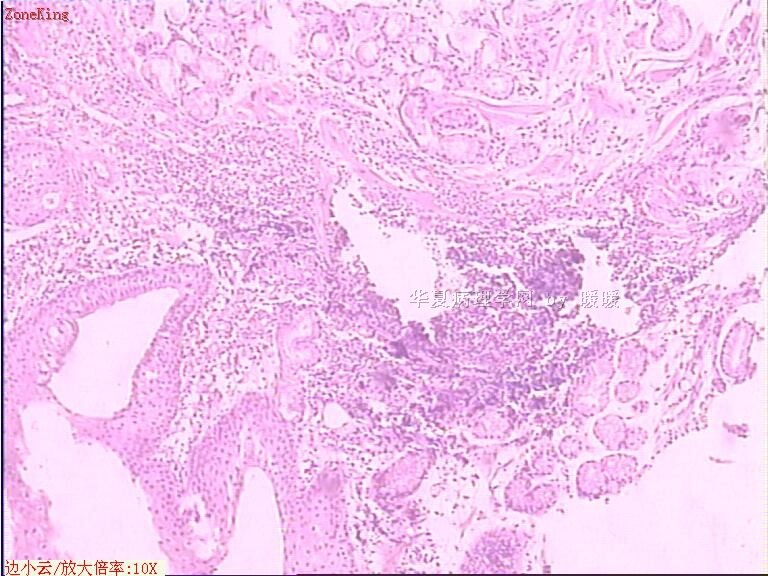

贲门息肉?

姓    名: ××× 性别:  女 年龄:  53

简要病史:  胃镜见,食道下段齿状线上可见一圆形隆起,有蒂,表面光滑,大小0.5X0.5X0.3cm.

各位老师,胃粘膜处出现的鳞状上皮有问题么?

• 贲门息肉?图4

图4

正好是齿状线腺鳞交界处粘膜

鳞状上皮没大问题,可能受炎症影响,稍有增生.

没有发现恶性证据,小心点儿可以拖个尾巴,譬如伴轻度异型增生。

可能是炎症刺激下上皮鳞状化生

本帖最后由 于 2009-11-21 09:51:00 编辑   谢谢各位老师指点,最终诊断为:贲门慢性炎症,伴局灶细胞轻度异型增生。